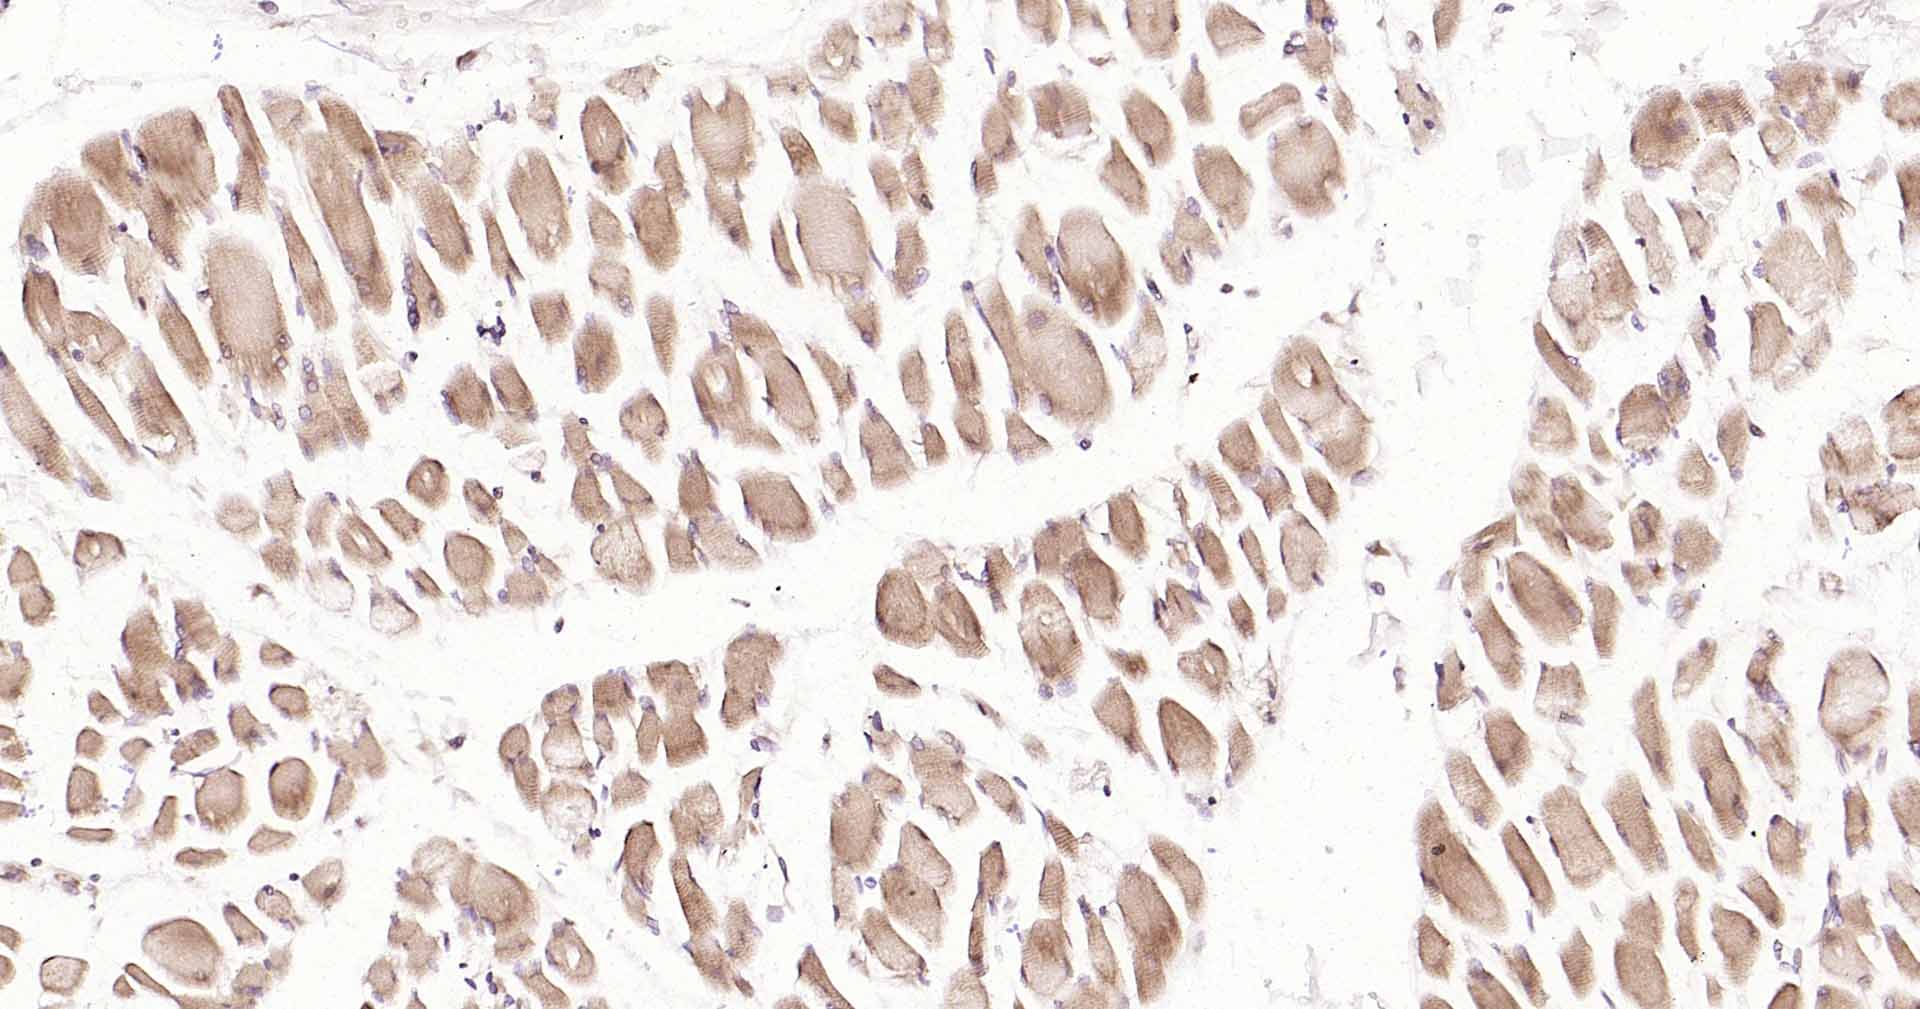

GADD153抗体-bs-20669RGADD153抗体-bs-20669RGADD153抗体-bs-20669RGADD153抗体-bs-20669RGADD153抗体-bs-20669RGADD153抗体-bs-20669RGADD153抗体-bs-20669RGADD153抗体-bs-20669RGADD153抗体-bs-20669RGADD153抗体-bs-20669RGADD153抗体-bs-20669R

IHC-PHuman, Mouse, RatCow1:50-200

IHC-FHuman, Mouse, RatCow1:50-200